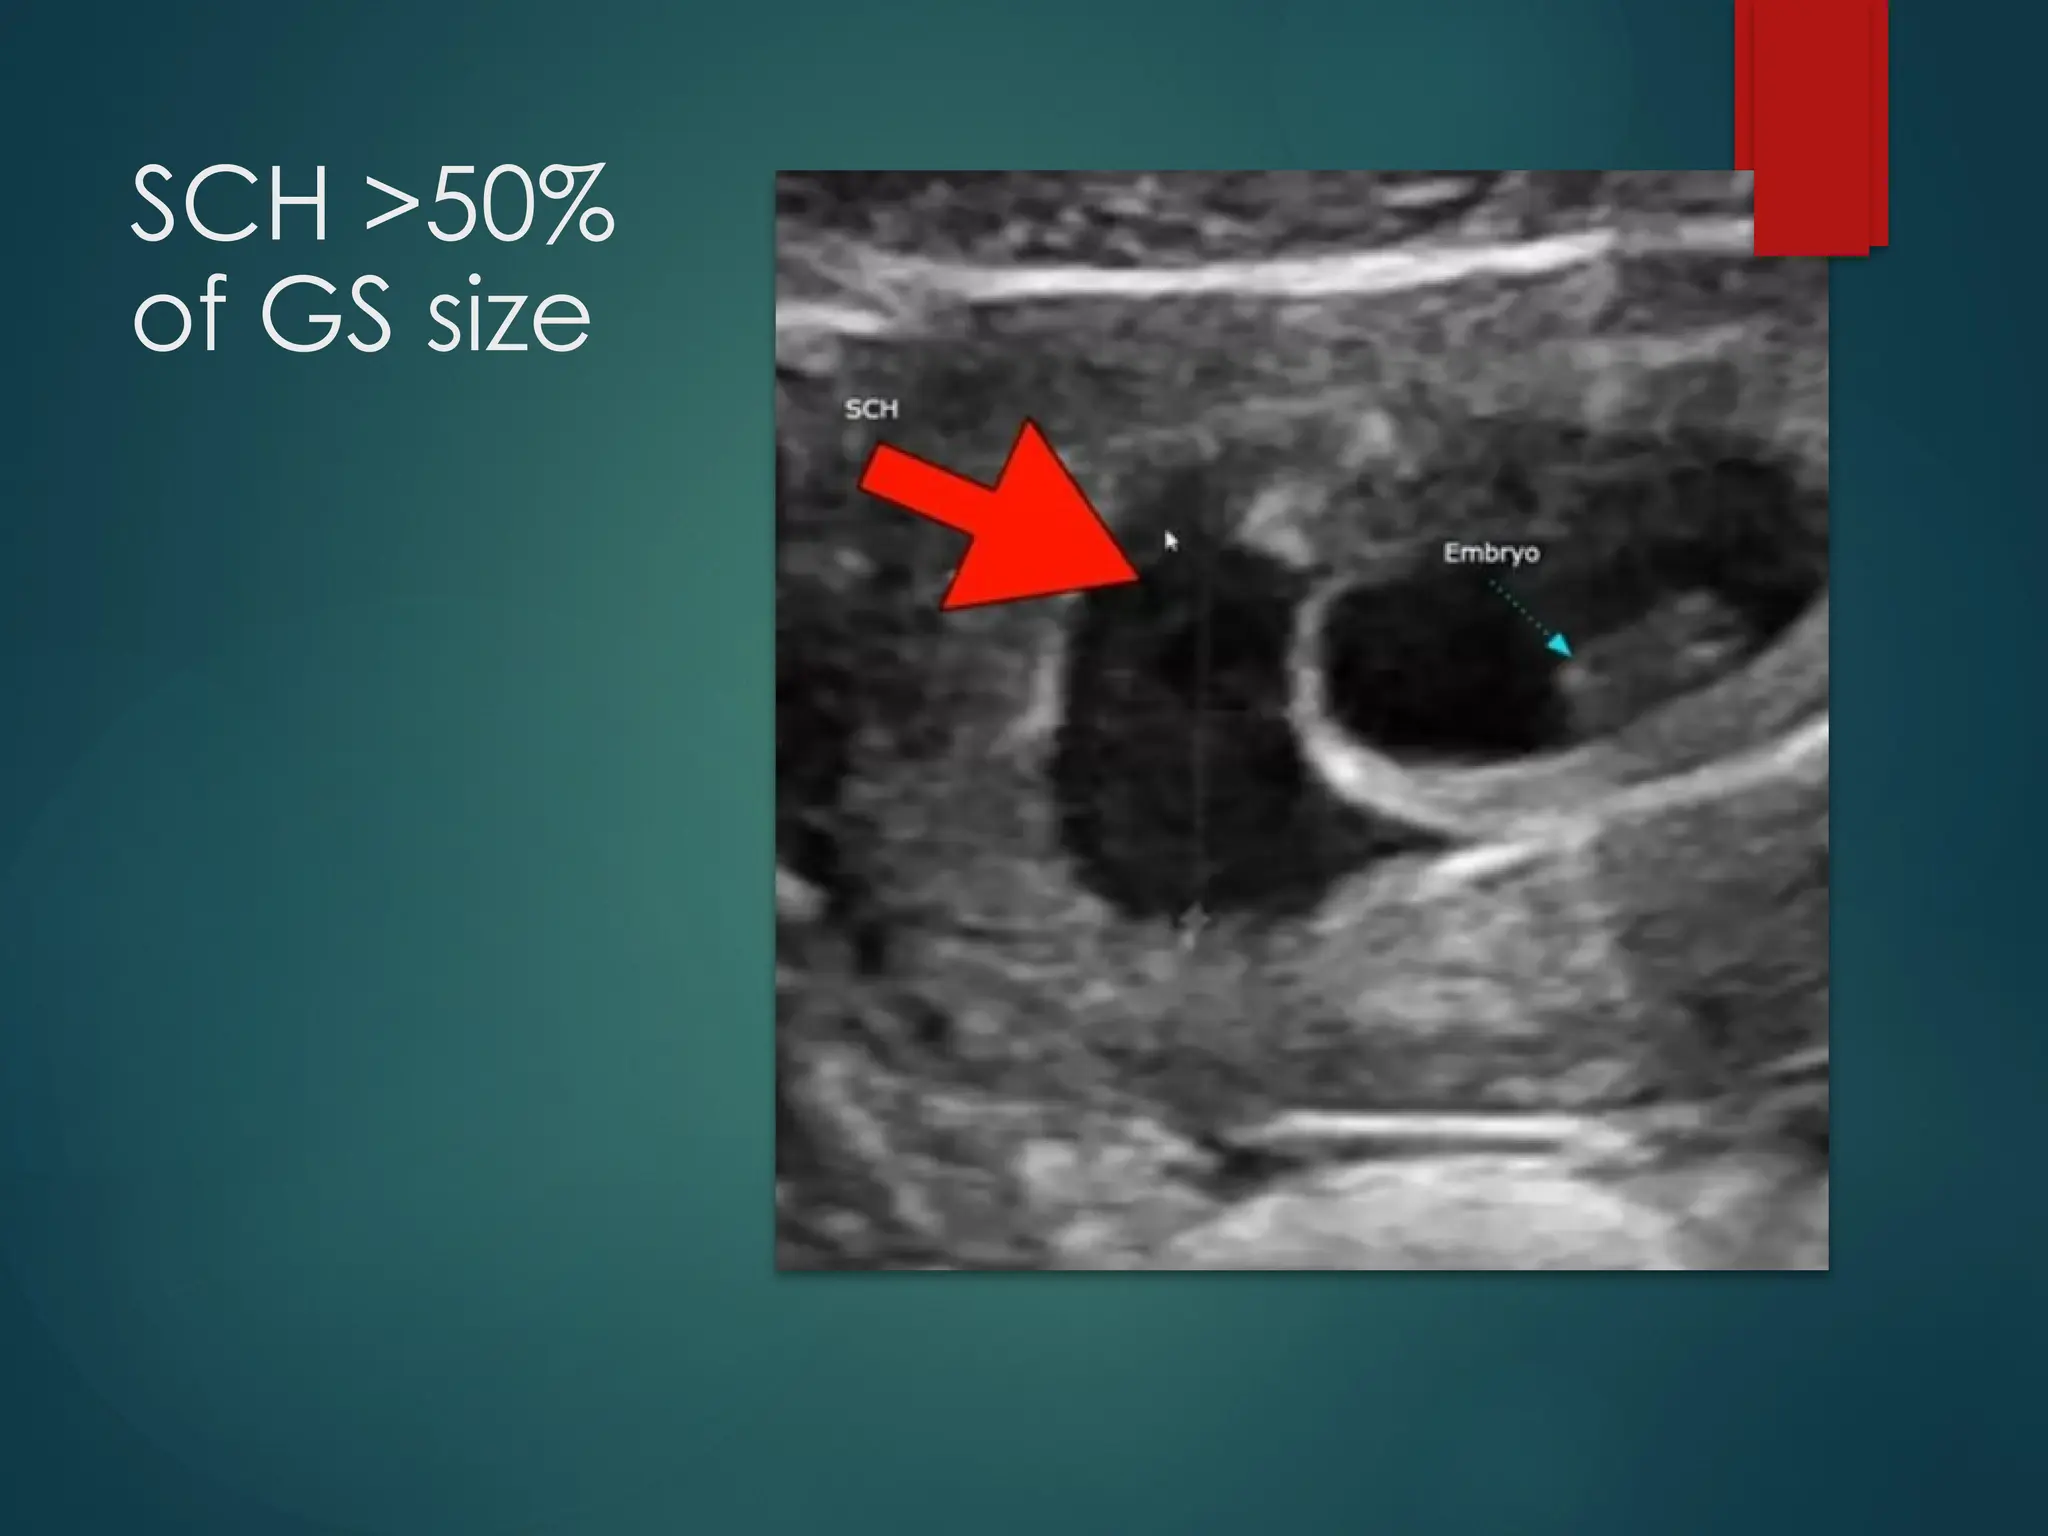

Grading of

Subchorionic

Haemorrhaage:

SMALL: <20% of the size of

gestational sac

Medium: 20-50% of the size of

Large: >50% of the size of

gestational sac (higher risk of

complications such as

miscarriage)

SCH >50%

of GS size